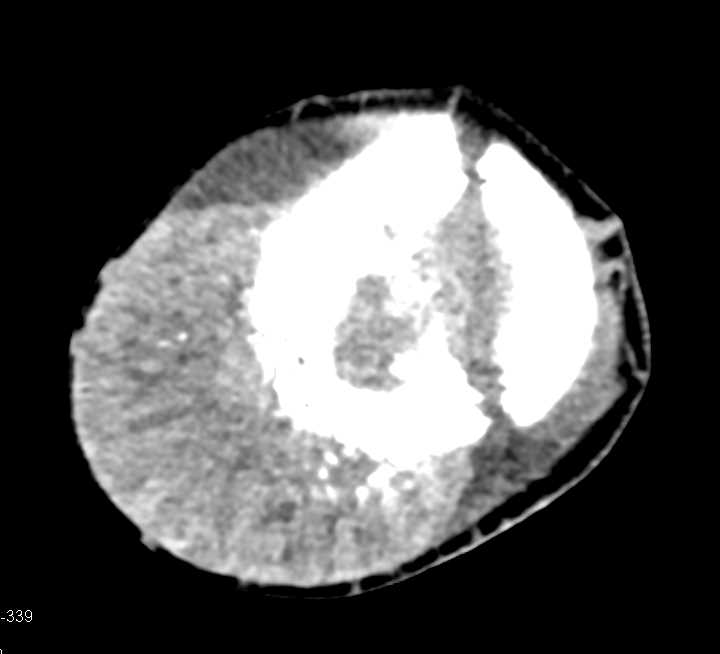

Mandibular Fractures